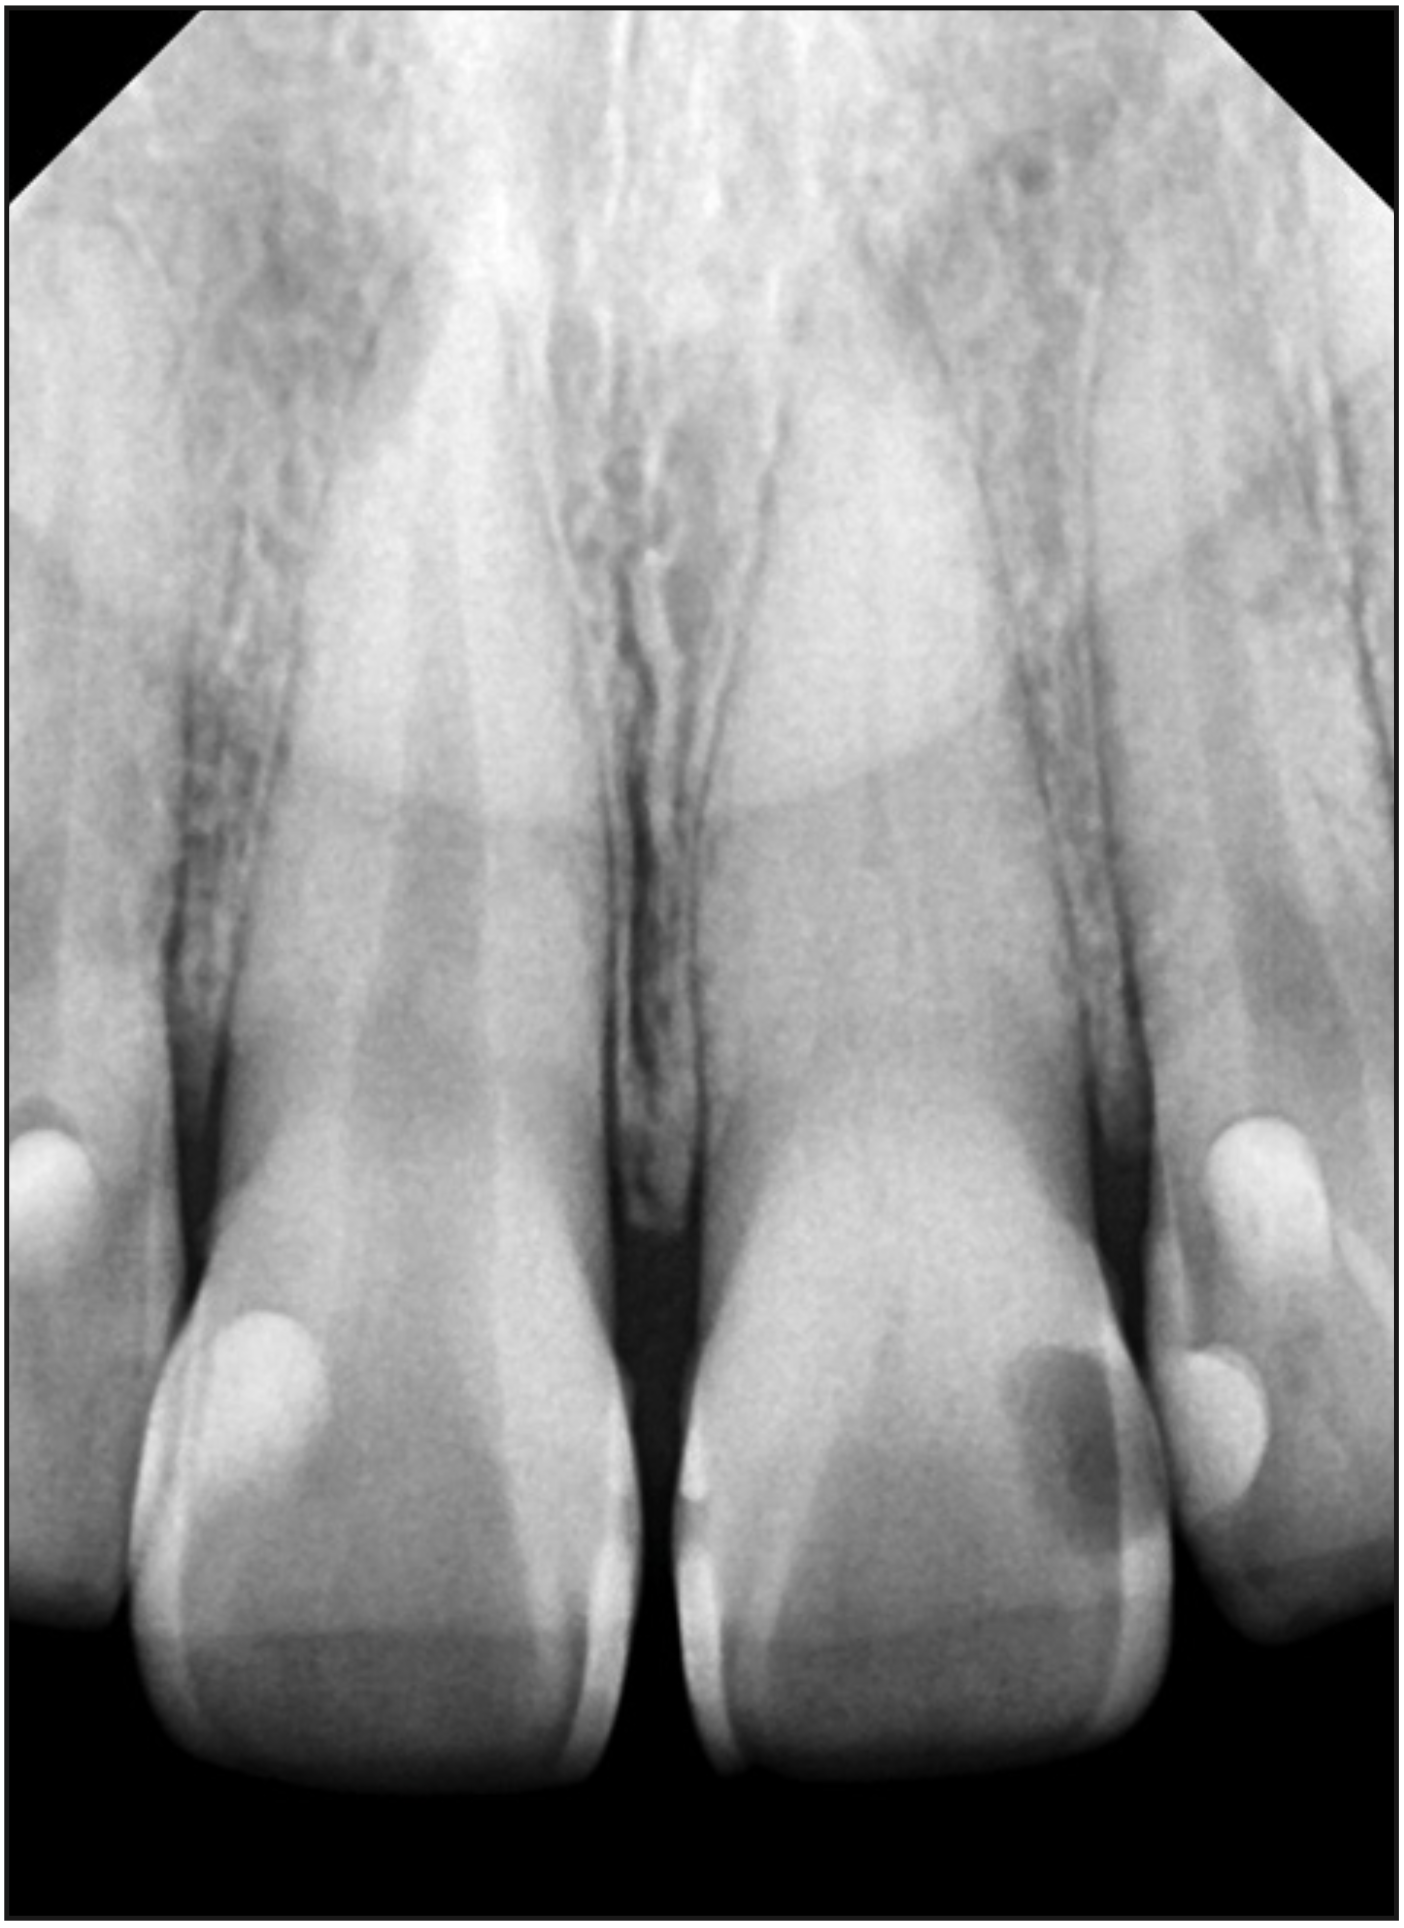

Al examen radiográfico, tanto la cámara pulpar como el conducto radicular se observan obliterados, además de la presencia de un área radiolúcida en el periápice del diente.

El diagnóstico del diente fue necrosis pulpar, y periodontitis apical sintomática.

Dada la complejidad del caso, se indico realizar una endodoncia guiada, por lo cual se realizó una tomografía computarizada de haz cónico (CBCT), y escaneo intraoral, para la confección de una guía estática (Figura 2). Posterior a la etapa de laboratorio, se realiza la prueba de la guía estática, para el chequeo de la estabilidad y del eje de acceso planificado.

Figura 2. Radiografía diagnóstico para evaluación de acceso guiado estático.